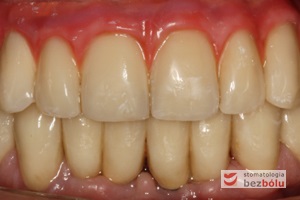

Pozytywna przemiana uśmiechu - odbudowa protetyczna na implantach - obraz kliniczny po terapii stomatologicznej

Pozytywna przemiana uśmiechu – obraz kliniczny po terapii stomatologicznej

Ostateczny efekt estetyczny wieńczący proces terapeutyczny - odbudowa protetyczna obu łuków zębowych przy zastosowaniu implantów Friadent Ankylos

Ostateczny efekt estetyczny wieńczący proces terapeutyczny – odbudowa protetyczna obu łuków zębowych przy zastosowaniu implantów Friadent Ankylos